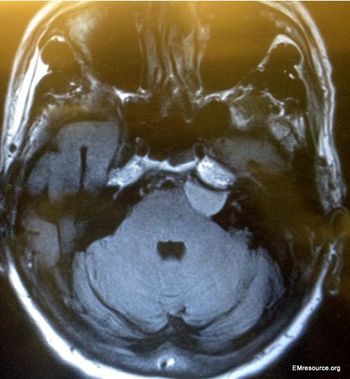

The patient denies vertigo, hearing change, headache or ear pain. Physical exam and past medical history are benign. What does the brain MRI tell you?

Signs and symptoms may raise suspicion for a posterior circulation stroke.